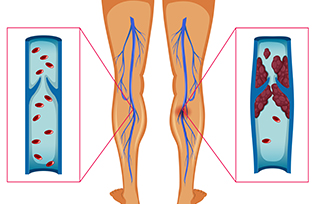

I.T.P

I.T.P ist eine Immunstörung, bei der das Blut nicht normal gerinnt. Dies ist eine Blutkrankheit, die durch eine Abnahme der Anzahl der Blutplättchen gekennzeichnet ist. Dieser Zustand wird heute häufiger als Immunthrombozytopenie (ITP) bezeichnet. ITP kann übermäßige Blutergüsse und Blutungen…